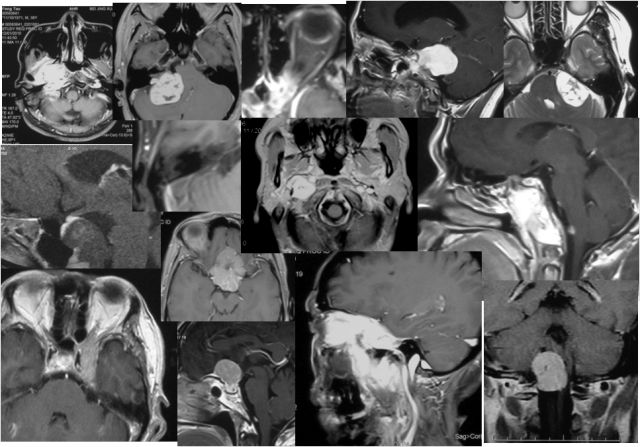

听神经瘤

手术体位个性化选择

嗅沟脑膜瘤

岩斜脑膜瘤

脑桥海绵状血管瘤

颈静脉孔区肿瘤

颈静脉孔内外沟通型神经鞘瘤

内镜经口+乙状窦后入路显微手术 分期手术

幕上下联合入路

颈静脉球瘤